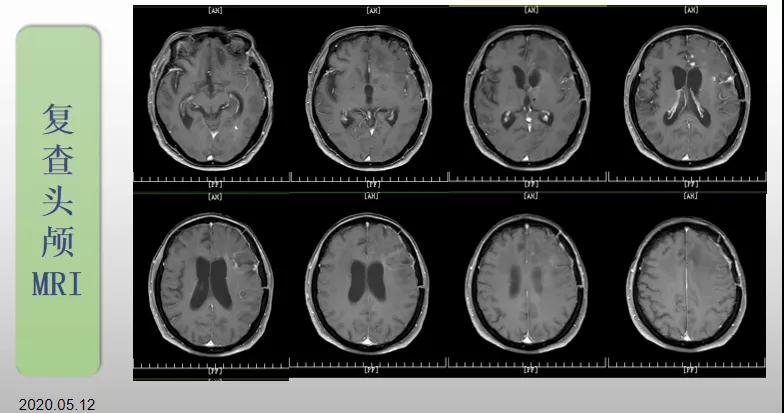

綜合治療 電場治療助70歲患者回歸正常生活

70歲的郝女士去年曾在外院查出“左額島葉”膠質(zhì)母細(xì)胞瘤(WHO Ⅳ級),并做了左側(cè)額島葉占位性病變切除術(shù)。術(shù)后進(jìn)行了同步放化療。由于治療條件有限,郝女士慕名來到我院就診。賀世明主任率領(lǐng)醫(yī)護(hù)團(tuán)隊立即為郝女士進(jìn)行了全面的檢查,決定為其進(jìn)行綜合治療 電場治療。經(jīng)過三個多月的綜合治療,患者復(fù)查頭顱MRI病變較前明顯縮小。出院時,郝女士神志清醒,睡眠飲食正常,說話很流利。“我是躺著進(jìn)來的,現(xiàn)在不用人攙扶,自己就可以走出病房了?!焙屡坷t(yī)護(hù)人員的手說。